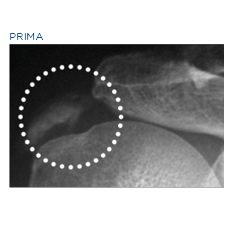

Las aplicaciones más comunes de la TERAPIA DE ONDA DE CHOQUE son el tratamiento de los dolores musculoesqueléticos crónicos resultantes de tendinopatías,puntos gatillo, eliminación de calcificaciones y estimulación de no uniones óseas.

CALCIFICAZIONE DELLA SPALLA, CONCESSA DA: BTL